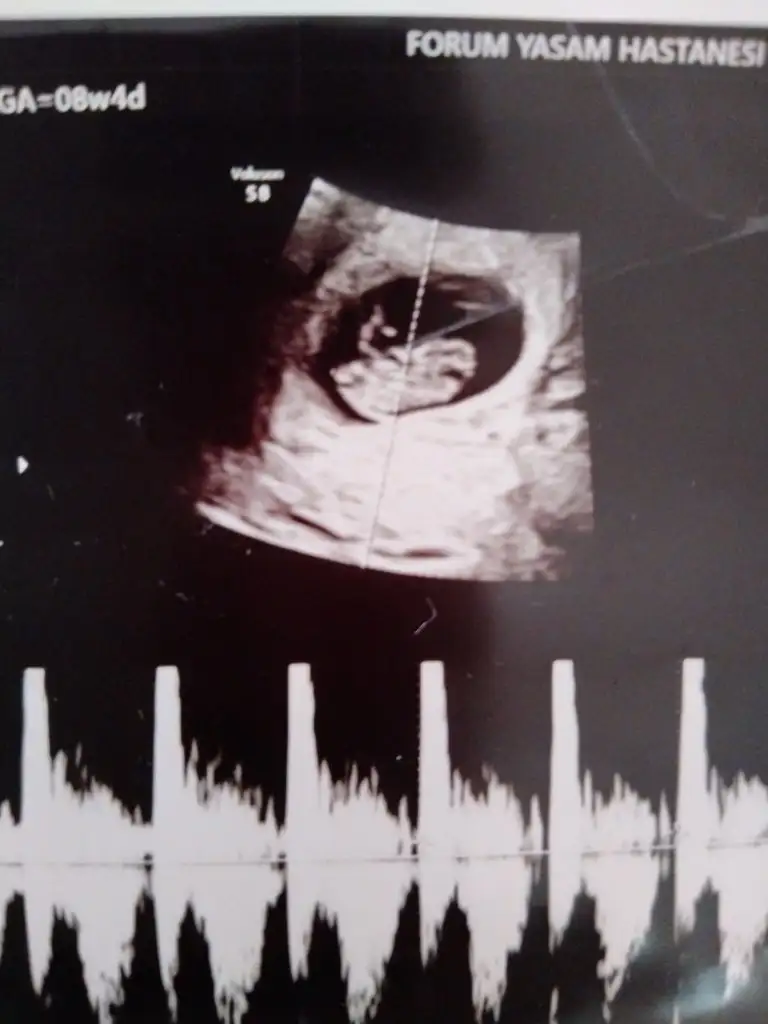

• 16793857404897884354304871002078.webp

16793857404897884354304871002078.webp

19,3 KB · Görüntüleme: 51